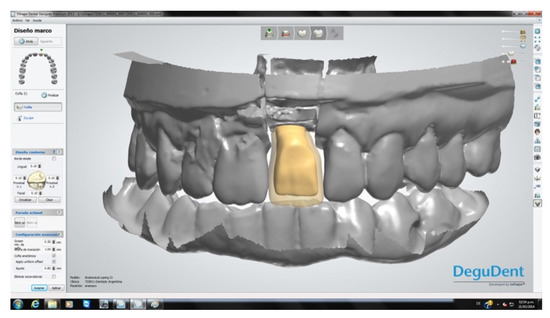

The crowns were fabricated using computer-aided design/computer-aided manufacturing (CAD-CAM, Cercon® Dentsply Sirona System, York, PA, USA; Figure 8). After a mock-up to guide color determination, the mesostructure was layered with ceramic having a thermal expansion coefficient compatible with the zirconia in the mesostructure, to produce the crown. The titanium base of the abutment was then joined to the internal surface of the CAD-CAM component by applying Single Bond Universal adhesive® (3M Espe, St. Paul, MN, USA) plus RelyX Unicem® cement (3M Espe, St. Paul, MN, USA) on both surfaces, to transform the system into a single component. Through this procedure, a screw-down crown was obtained, as outlined in the treatment plan. Finally, each crown was screwed applying a torque of 32 N/cm and the palatal access was sealed with a composite of the same color as the porcelain (Figure 9). All patients followed a maintenance program (Figure 10).

Figure 8.

CAD-CAM restoration design.